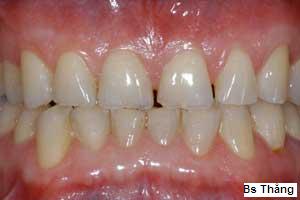

![]() | Mòn rìa cắn các răng cửa |